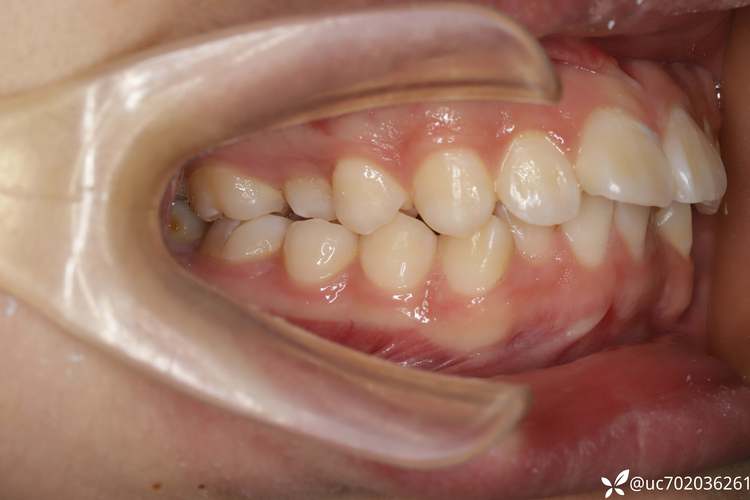

拔除2号牙后,正畸医生会通过矫治器(如传统托槽、自锁托槽、隐形矫正器等)引导牙齿按预设方向移动,最终实现牙列稳定与功能平衡,其核心原理是“利用拔牙间隙解决主要问题”,具体流程如下:

- 关闭拔牙间隙期(6-18个月):通过“滑动法”或“关闭曲法”,将后牙前移,前牙内收,逐步关闭拔牙间隙;此阶段是矫正的关键,需定期复诊调整矫治力,确保牙齿移动方向准确;